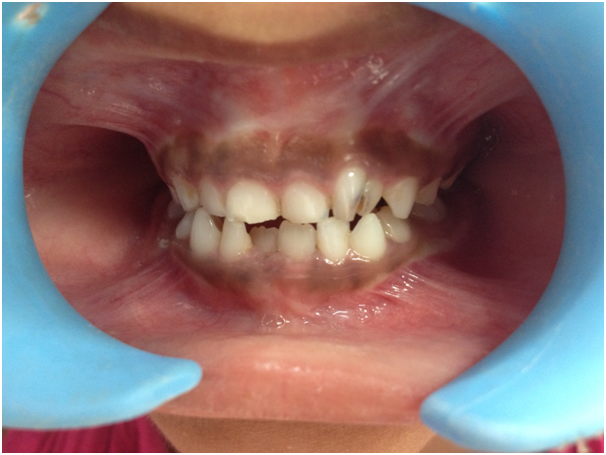

A seven-year-old girl reported to the Department of Pediatric and Preventive Dentistry with the chief complaint of decayed tooth in the upper arch. The medical history of the child patient was insignificant and there was no family history of dental anomalies. An intraoral examination revealed the presence of complete primary dentition alongwith mandibular permanent first molars and incisors and presence of double tooth in relation to the maxillary left primary lateral incisor (Figure 1). Radiographic examination i.e. OPG revealed that the enlarged bifid crowns were due to fused 62 i.e. maxillary left primary lateral incisor and supernumerary tooth (Figure 2). The diagnosis was fusion caused by union of the maxillary primary left lateral incisor and a supernumerary lateral tooth. Restoration of the primary left lateral incisor and supernumerary lateral tooth was done with glass ionomer cement (GIC) restoration and fused primary teeth were retained (Figure 3). The parents of the child patient gave no history of trauma in the anterior region and consanguineous marriage. A thorough general examination was carried out to rule out the presence of any associated syndrome. The patient was advised to maintain the regular follow-up visits to observe any deviation from normal eruption pattern.

Figure 1 Preoperative intraoral view presenting two crowns in relation to maxillary primary left lateral incisor.